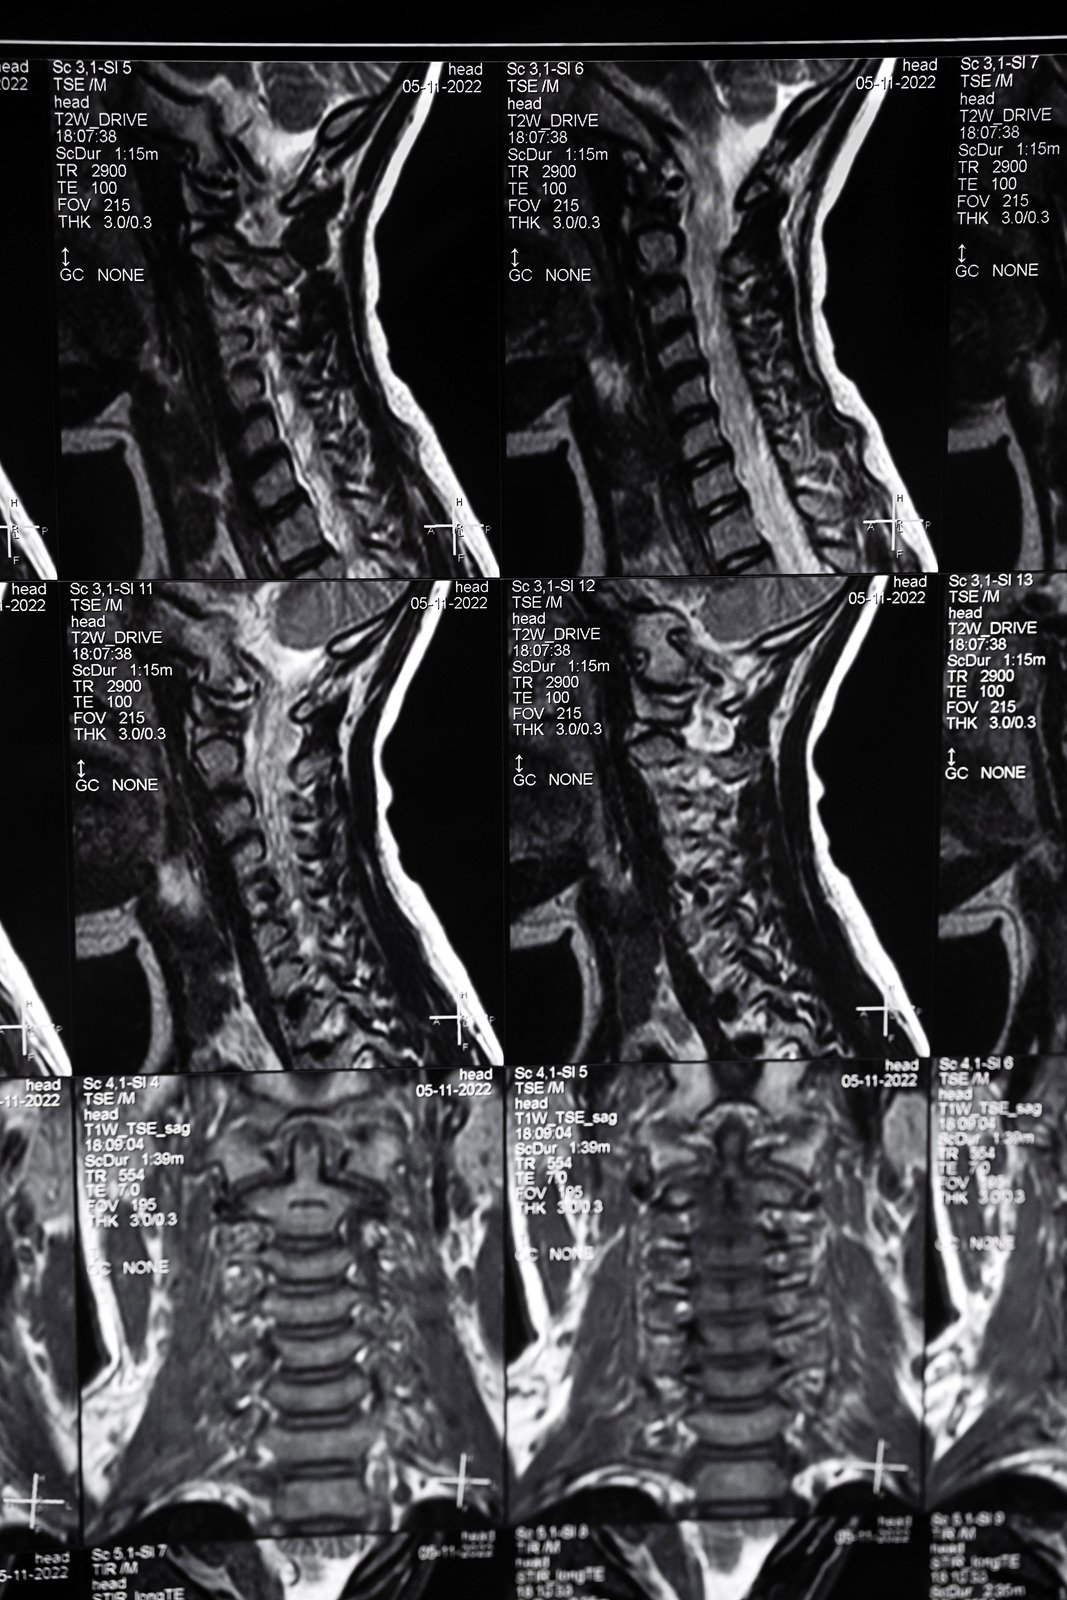

경추 디스크 질환 이해하기

경추 디스크 질환은 목 부위의 척추 사이에 있는 디스크가 손상되어 발생하는 상태입니다.

척추 디스크는 척추뼈 사이에 위치하여 충격을 흡수하고 척추의 움직임을 원활하게 해주는 역할을 합니다.

이 디스크가 탈출하거나 손상되면 주변 신경을 압박하여 목 통증, 팔 저림, 근육 약화 등의 증상을 유발할 수 있습니다.

경추 디스크 질환의 증상

경추 디스크 질환은 다양한 증상을 나타낼 수 있으며, 이는 디스크의 손상 정도와 위치, 압박받는 신경의 종류에 따라 달라집니다.